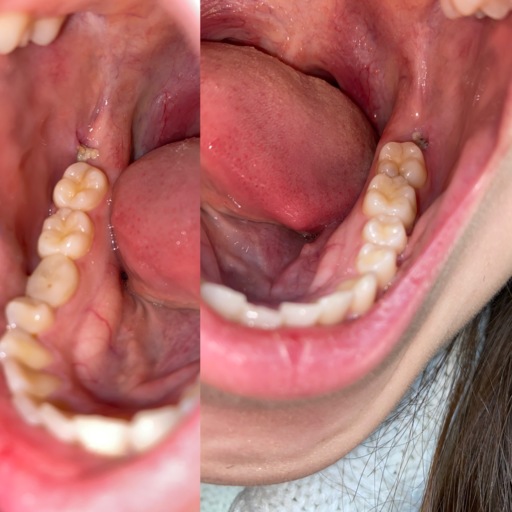

Is this an infection?

I just had all 4 wisdom teeth removed 3 days ago and this is on the bottom left side and I can’t tell what it is. It is only on the left bottom side and from trying to look it up on the internet I can’t tell if it’s an infection or not.